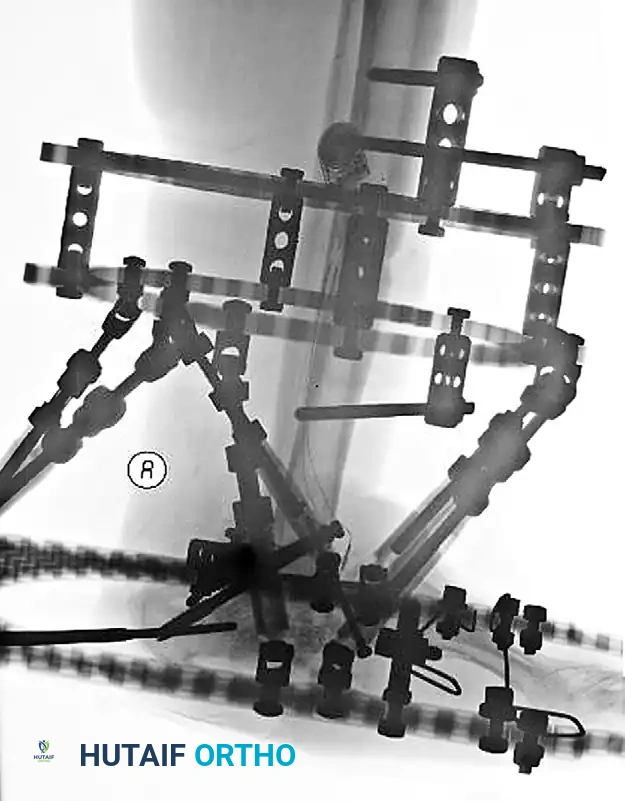

2. External Fixation: A hybrid or Ilizarov fine-wire external fixator is applied to span the defect, provide rigid stability, and allow for daily wound care and soft tissue reconstruction.

Image

FIGURE 85-21 A and B: Charcot arthropathy of the ankle complicated by severe osteomyelitis.

FIGURE 85-21 F: Application of a hybrid external fixator to stabilize the limb and maintain length following talectomy.

FIGURE 85-21 G and H: Postoperative radiographs showing the hybrid fixator in place, providing rigid stabilization while the soft tissue envelope heals.